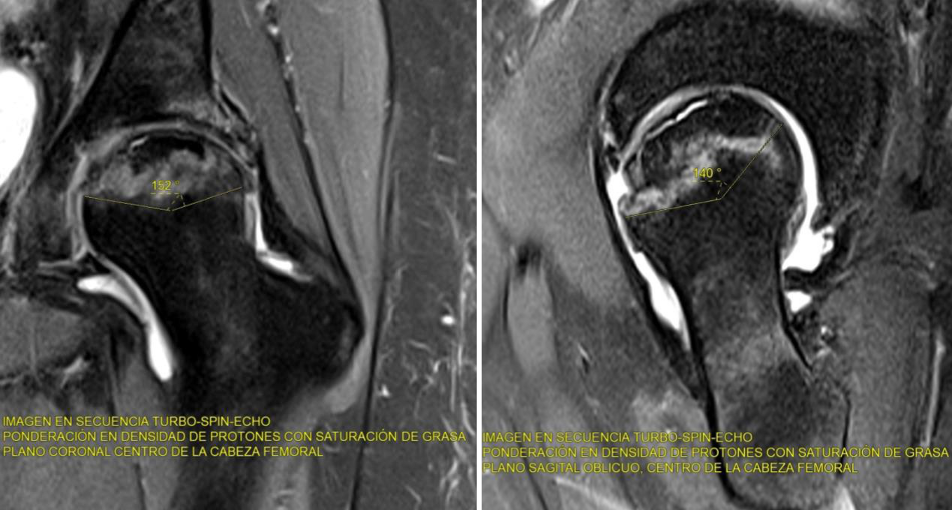

La resonancia magnética (RM) es el método más sensible y específico para detectar la necrosis en estadios iniciales. Permite identificar cambios precoces en el hueso trabecular, edema óseo y zonas de necrosis antes de que sean visibles en radiografías. El signo más característico en RM es el "doble anillo", una línea hipointensa periférica rodeando una zona hiperintensa, que representa el tejido necrótico y la reacción reparativa.